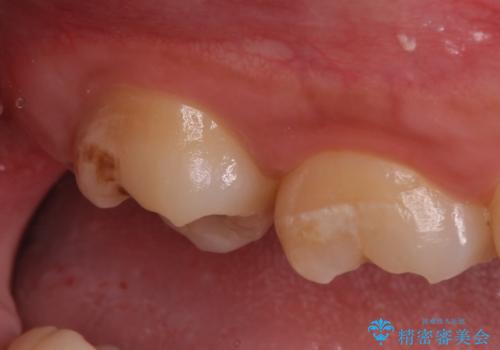

- 親知らず抜歯をご希望で来院されましたが、手前の歯が歯ぐきに覆われていたため抜歯と同時に歯ぐきの除去を行います。

歯の高さ十分がないと十分なブラッシングができなかったり、被せ物をする際に不利になってしまいます。

そのような時は周りの歯茎を除去することで歯の高さを出すことができる場合があります。